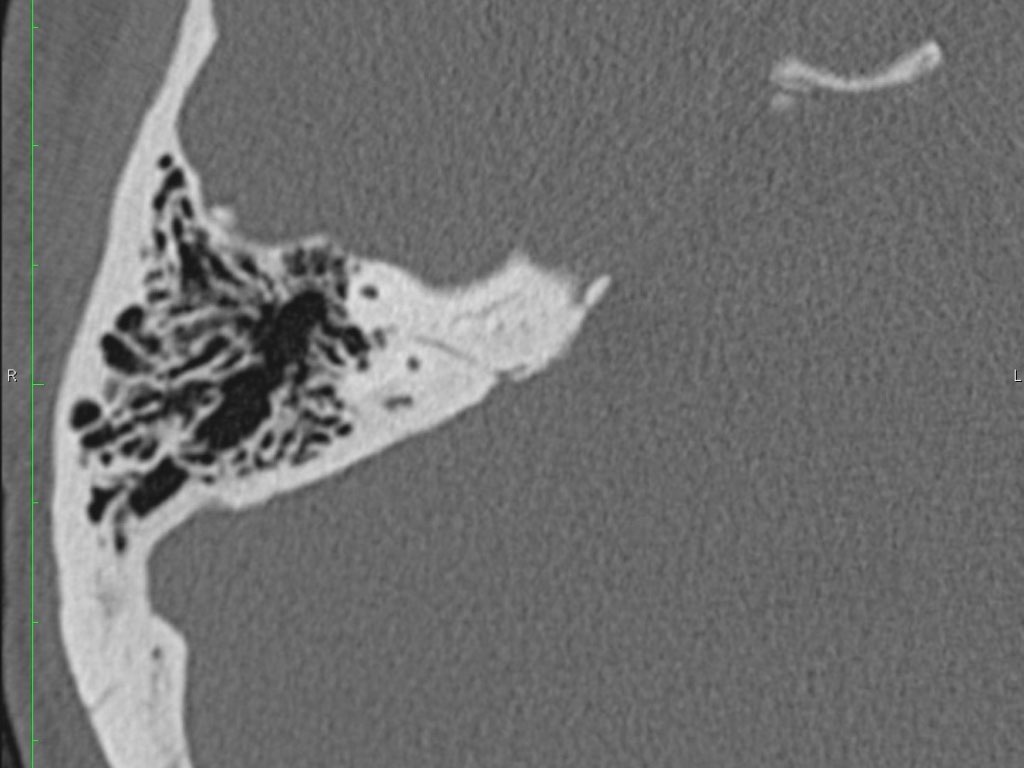

Trong bài tổng quan này, chúng tôi trình bày giải phẫu bình thường trên mặt phẳng cắt ngang (axial) và mặt phẳng cắt đứng ngang (coronal) của xương thái dương thông qua việc duyệt qua các hình ảnh.

Một số cấu trúc được thảo luận chi tiết hơn với trọng tâm là các bệnh lý liên quan.

Giải phẫu xương đá trên mặt phẳng cắt ngang (Axial)

Cuộn qua các hình ảnh.